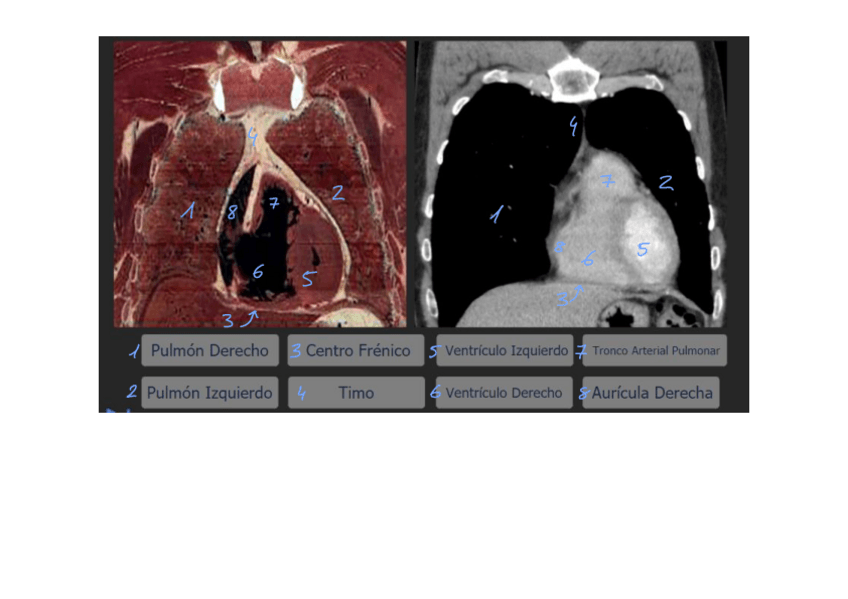

Imagenes-de-Torax-con-nombres.pdf

Practicas-12-y-13-resueltas-con-nombres.pdf

Imagenes-de-Torax-con-nombres-2.pdf